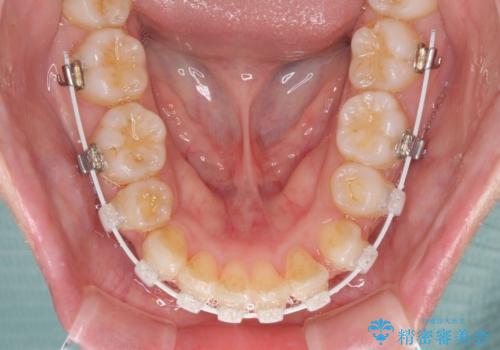

- 矯正装置

- 審美装置

- 2年4ヶ月

- 10-30回

- 前歯のデコボコと口元の突出感を気にして来院された患者様です。

上下左右第一小臼歯4本を抜歯し、ワイヤー装置にて口元を引っ込めるよう矯正治療を行うこととしました。